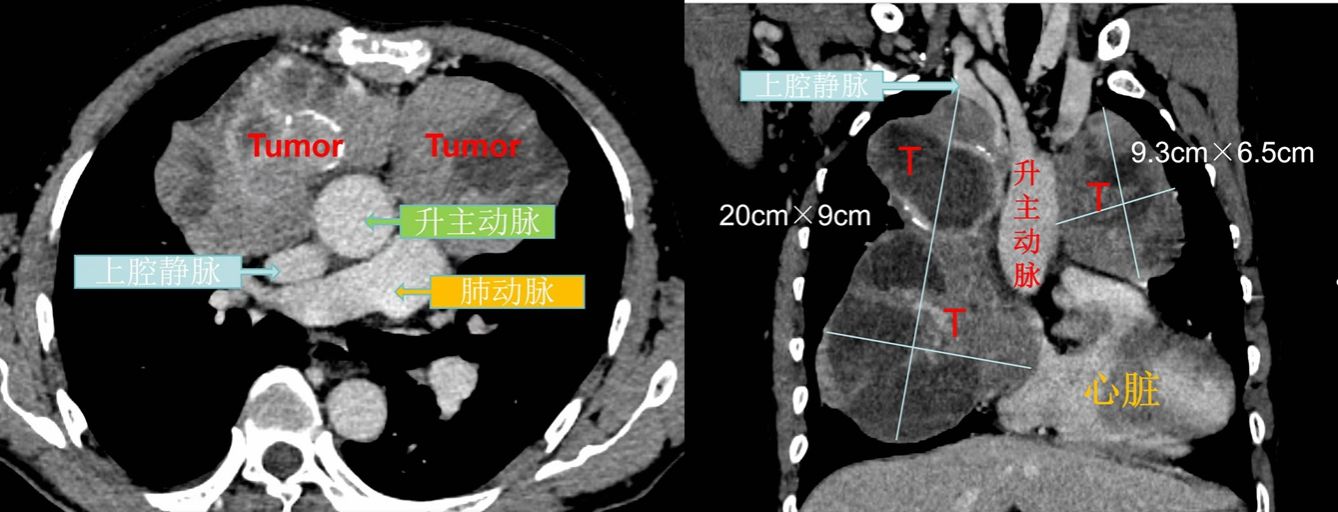

患者在家人的陪同下慕名来到素股 胸部肿瘤外科就诊,随即入院治疗,经CT引导下纵隔肿瘤穿刺活检,病理提示:“纵隔”神经内分泌瘤。胸部增强CT检查提示患者前上纵隔肿瘤大小近18cm×8cm,并成不均匀强化,左无名静脉、上腔静脉明显受压、狭窄,心包受累,心脏受压。如果不及时治疗,瘤体会继续增大,并进一步压迫心脏、大血管、气管等重要脏器,严重影响患者的生活质量,威胁患者的生命安全。

经多学科讨论(MDT)后,建议先行化疗,肿瘤缩小后再评估手术。经3周期化疗后,肿瘤原发耐药,疗效不佳。复查CT发现肿瘤进行性长大,CT提示纵隔肿瘤最大截面“20cm×9cm”。患者心脏及纵隔大血管受压明显,间歇气短症状加重。纵隔神经内分泌瘤部分具有生长迅速、呈恶性生长的特点,若再不接受手术,患者将随时可能出现呼吸和心脏骤停。